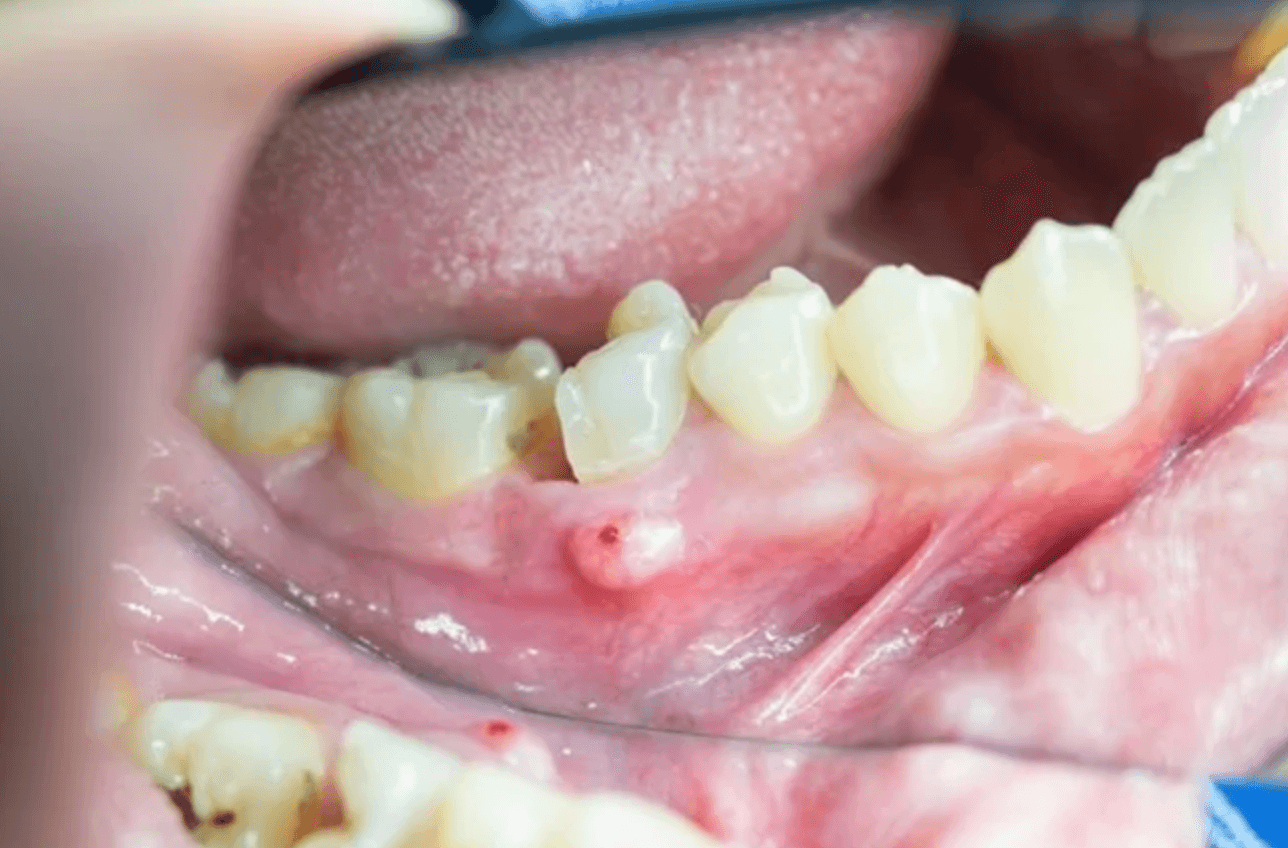

치아뿌리 깊은 곳에 염증이 생겨 잇몸 위로 농양이 차올라 피부가 부풀어 올라오는 경우 치근단 농양으로 치료하지 않고 방치하게 되면 염증이 주변의 뼈를 녹이는 것은 물론 치아 상실의 원인 될 수 있습니다. 이러한 치근단 농양 치료 수술 비용 경험에 대한 후기를 남겨 봅니다.

치근단 농양

글쓴이 같은 경우 치근단 농양으로 현재 2개의 임플란트를 하였으며, 하나는 치근단절제술로 몇개월 잘 유지되는가 싶더니 다시 염증이 잇몸을 뚫고 나와 현재 다시 치근단절제술을 할지 아니면 뽑고 임플란트를 할지 고민을 하고 있습니다.

이처럼 치근단 농양은 치료를 한다고 모두 정상으로 돌아오는게 아닙니다. 다시 재발하여 염증이 차오를 수 있으며, 결국 치근단절제술도 통하지 않아 치아를 발치하고 임플란트를 해야 됩니다.

- 만성적 잇몸 누공 발생

치근단 농양 수술 후기

치근단 농양 치료 수술은 치근단절제술이라고 하여, 치아뿌리를 절단하여 더 이상 염증이 나오지 않게 치료하는 것입니다. 이러한 치료를 하였다고 하여 100% 성공이 되는 것이 아니기 때문에, 재발할 가능성 또한 높습니다.

글쓴이 또한 이번에 재발하여 다시 재수술을 하자니 치근단절제술 하기가 생각보다 쉽지 않고 통증이 생각보다 심했습니다. 저는 염증이 심해서 뼈를 많이 녹여서 뼈이식을 했는데 얼굴이 거이 1주일 이상 부어 있었거든요.

수술 후에도 잇몸이 아직도 크라운 쪽으로 100% 내려오지 않아 약간 치아와 잇몸사이 구멍이 있어 자세히 보면 정말 보기가 싫습니다. 그래서 차라리 이번에 그냥 뽑아버리고 임플란트로 할까 그런 생각도 드는데, 최대한 살려보고자 치과 의사와 현재 고민 중인 치아입니다.